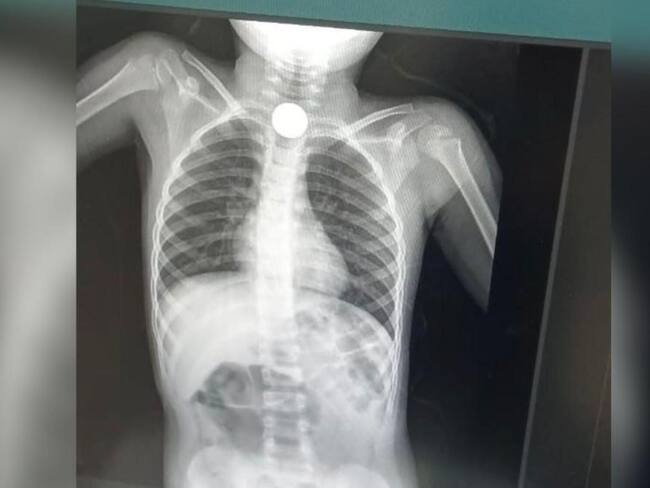

Placa del menor/ Jairo López